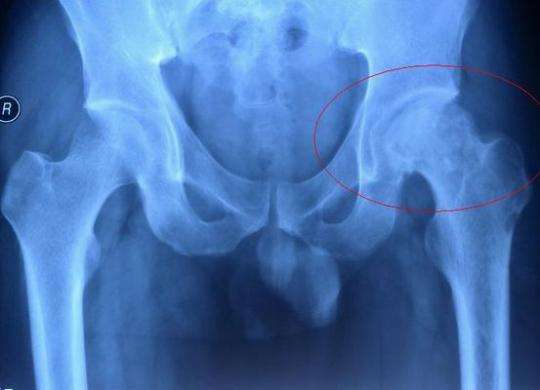

成人先天性髖關節脫位,也稱為成人髖臼發育不良,是一種先天性的發育異常,是引起髖關節疼痛的常見原因之一,也是髖關節骨性關節炎的重要致病因素。一般認為該病在女性的發病率要高于男性,男女比例約為1:5,并且在1/4的患者中存在家族史。在正常的髖關節,碗狀的髖臼對球形的股骨頭覆蓋良好,髖臼和股骨頭之間還有一些軟骨和關節囊起到穩定的作用。當髖臼發育不良時,髖臼碗變淺并且向外翻轉,導致它對股骨頭的包容性變差,股骨頭容易向外上方移位,發生半脫位。